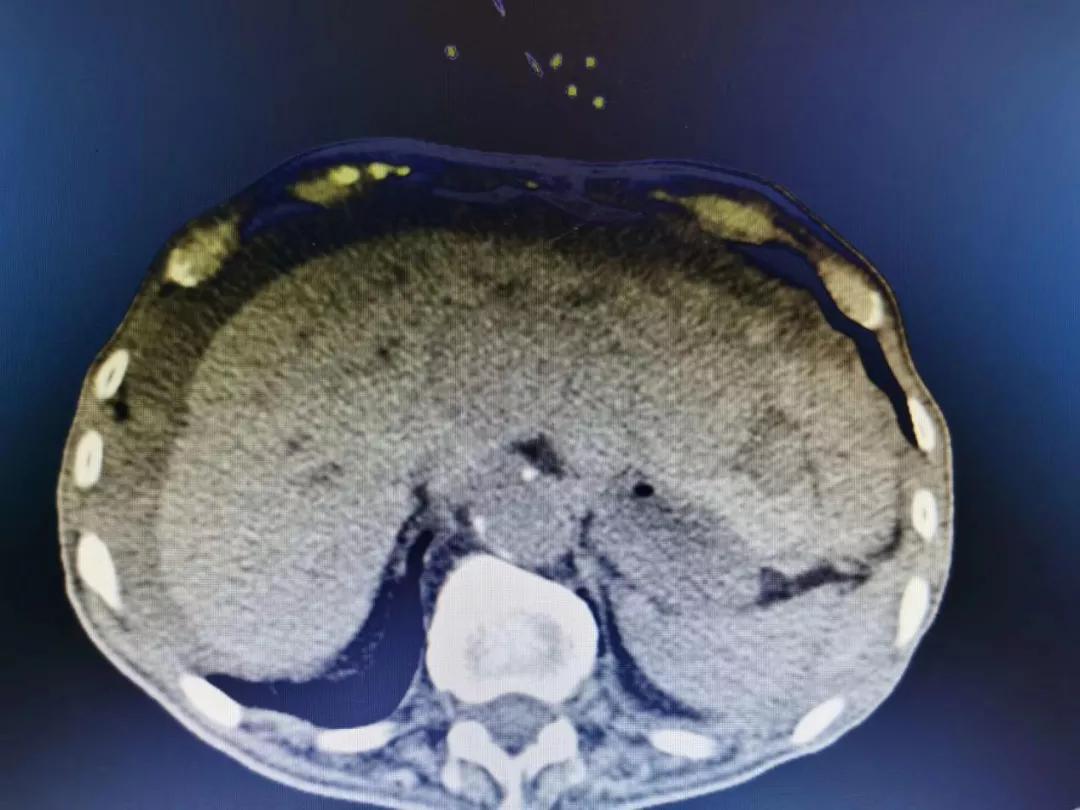

肝破裂 亳州市人民医院 影像中心

ct表现肝是腹部外伤时易累及的实性器官,仅次于脾,肝创伤的原因包括

ct表现包膜下破裂中央破裂完全性破裂分类脾破裂肾脏泌尿系统胰腺肝脏